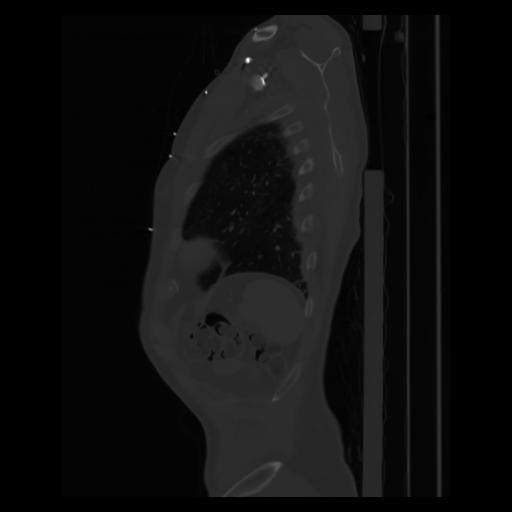

30 CUERPO,CE,Sagittal,3.000,CUERPO,Sagittal,